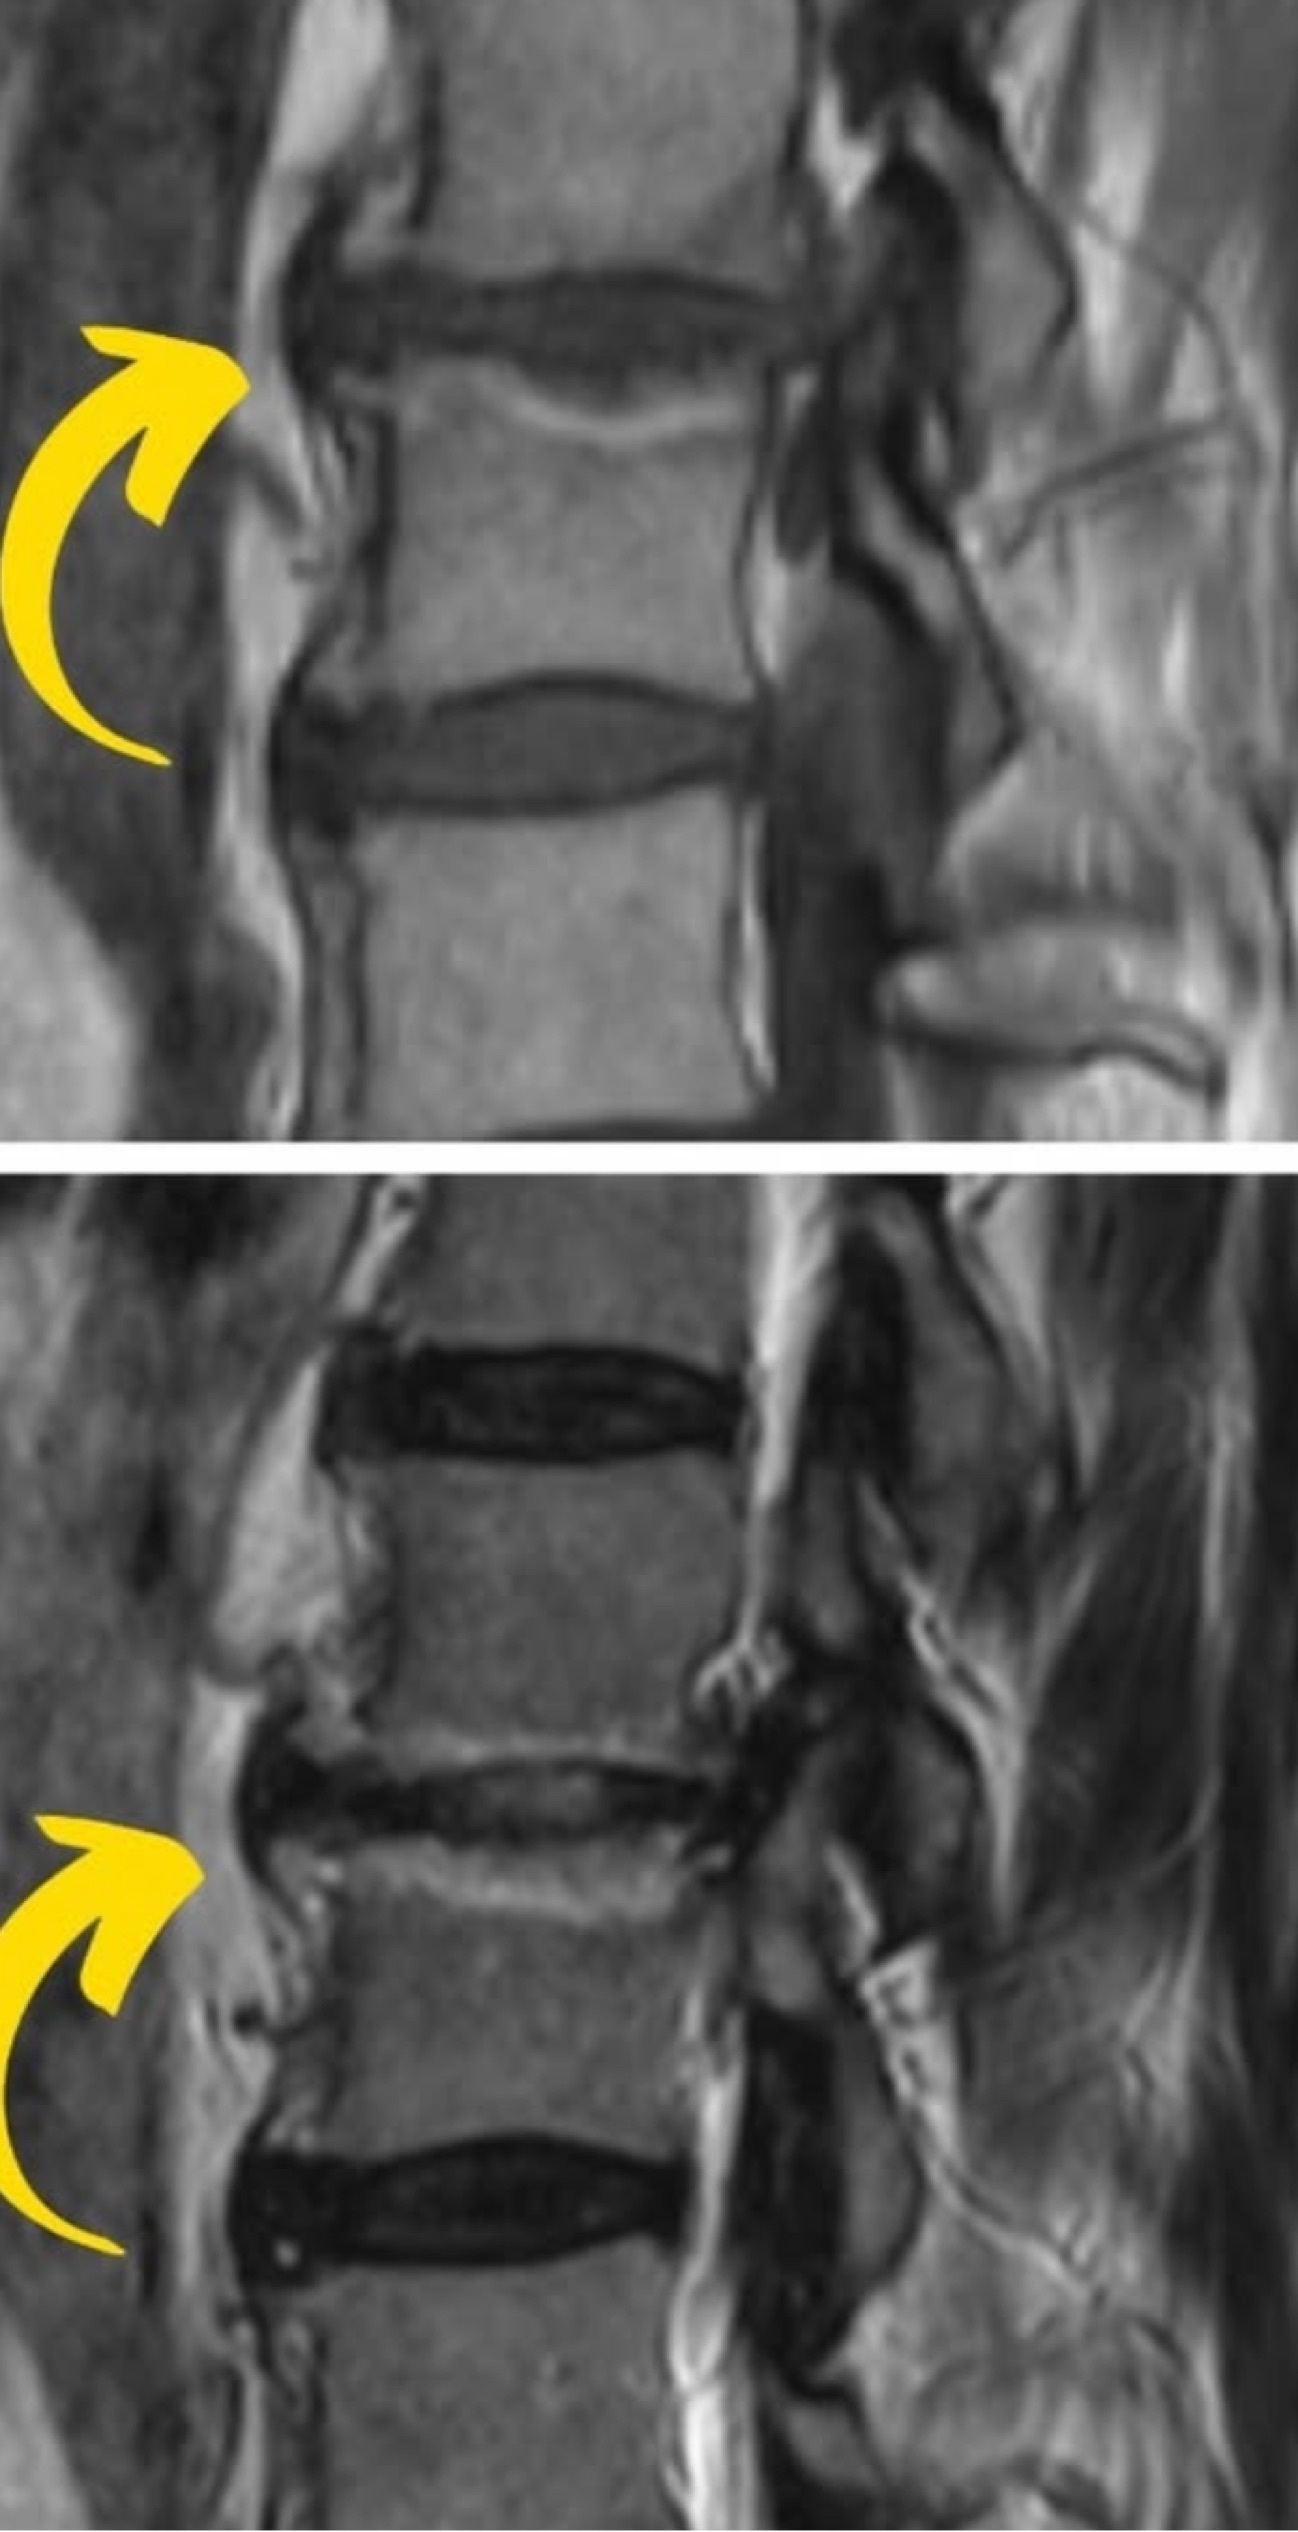

Qual o diagnóstico?

A

Vértebra plana